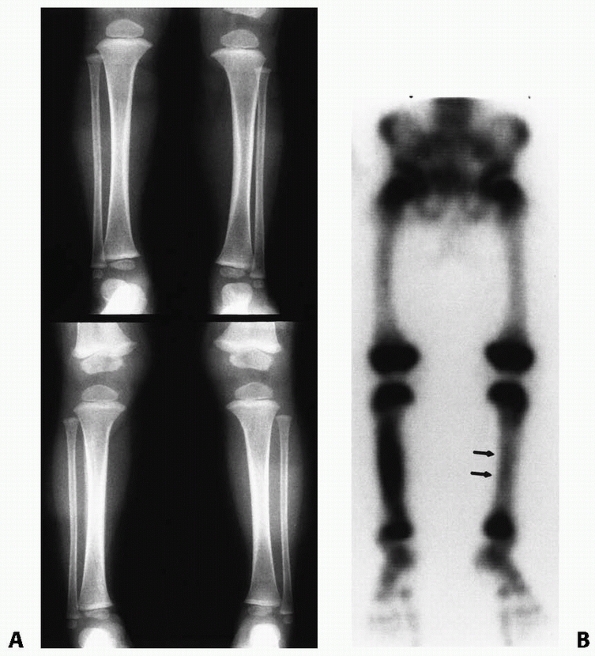

![]() |

|

FIGURE 25-33 A 50-month-old child with a middle one-third transverse tibial fracture and a plastically deformed fibular fracture. A. Lateral view shows 20-degree posterior angulation. B. The deformity is still 15 degrees 4 years after the injury.